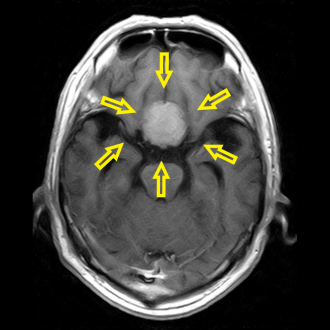

頭部MRIで脳腫瘍を認め、総合病院の脳神経外科に紹介しました。